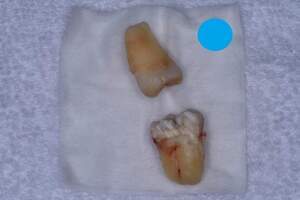

左上下の親知らずが

大きな虫歯になっていた症例

- 抜歯前写真(レントゲン、CT等)

- 抜去歯の写真

| 年齢 | 20代・女性 |

|---|---|

| 主訴 | 右下の親知らずを抜きたい |

| 親知らずの生え方 | 半分埋まっている |

| 抜歯時間 | 60分 |

| 費用 | 約6,000円(CT代含む) |

| 抜歯内容 | 右下親知らずが半分埋まっているため、汚れが溜まりやすく気になる為患者様のご希望により抜歯しました。 このケースでは事前にCTを撮影し、歯の位置、神経との位置関係を確認してから抜歯を行っています。 抜歯後、一週間は腫れと痛みがありましたが鎮痛剤を飲んで対応して頂き、糸取りをする頃には痛みや腫れは無くなり、患者様も安心しておられました。 |